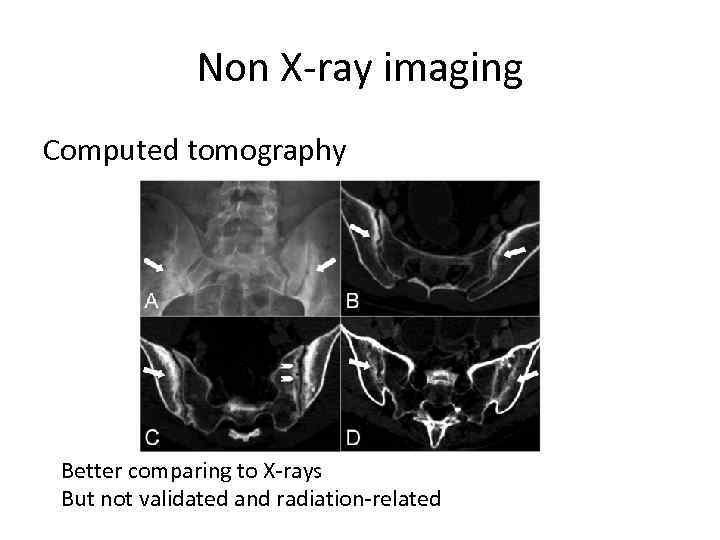

Non X-ray imaging Computed tomography Better comparing to X-rays But not validated and radiation-related